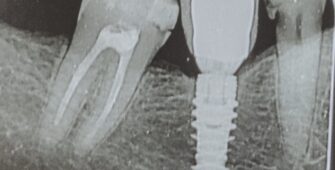

Implantes dentales Cualquier problema que aparezca en nuestra boca puede acabar afectando a nuestra salud general. Un claro ejemplo es la pérdida de una pieza bucal que puede ocurrir por periodontitis, traumatismos dentales o por caries profundas imposibles de restaurar. Este problema no solo afectará a nivel estético, sino también a la hora de comer….